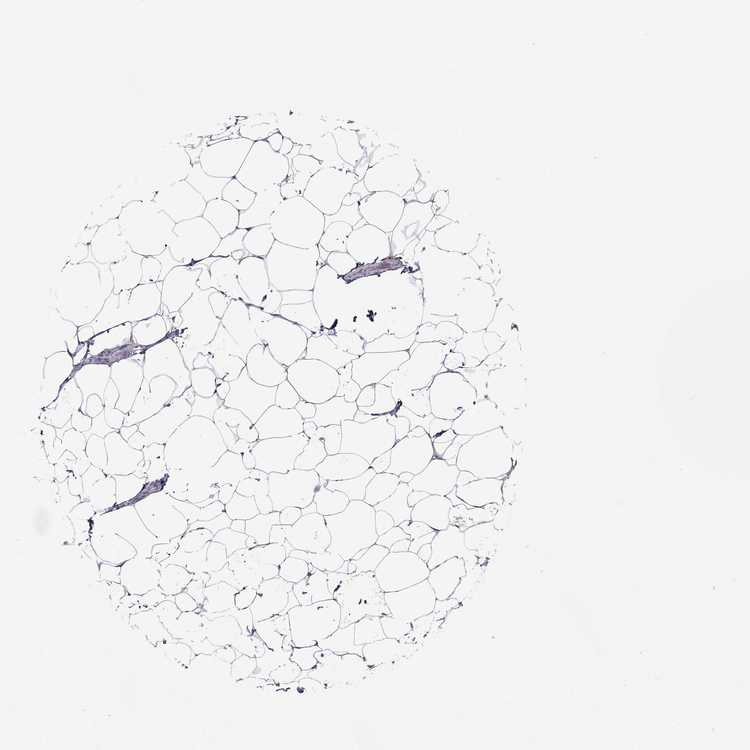

TISSUE PRIMARY DATA BREAST Show tissue menu

BREAST - Antibody stainingi

Antibody staining in the annotated cell types in the current human tissue is reported as not detected, low, medium, or high, based on conventional immunohistochemistry profiling in selected tissues. This score is based on the combination of the staining intensity and fraction of stained cells.

Each image is clickable and will lead to virtual microscopy that enables deeper exploration of all samples and also displays staining intensity scores, fraction scores and subcellular localization as well as patient and tissue information for each sample.

Antibody HPA049408Antibody HPA055446

Adipocytes Not detectedNot detected

Glandular cells MediumLow

Myoepithelial cells Not detectedNot detected